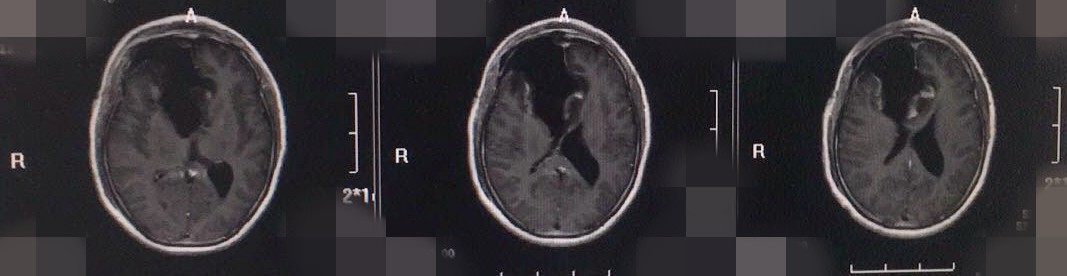

术后影像

术后,患者症状改善明显,且无不适。目前患者已经出院调养。